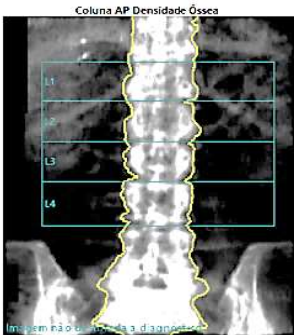

Sobre o exame a seguir pode-se afirmar:

Assinale a alternativa correta.